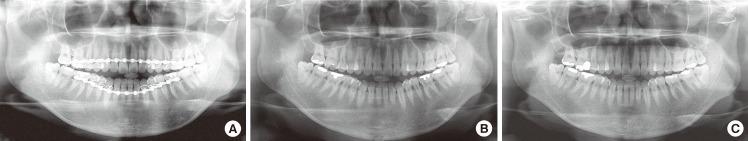

在治疗下颌髁突骨折时,可采用闭合复位的保守治疗或切开复位的手术治疗。下颌髁突骨折的处理在口腔颌面创伤领域仍是一个持续存在争议的问题。对于每种类型的髁突骨折,必须考虑牙齿的存在情况、骨折高度、患者适应性、患者咀嚼系统、咬合功能紊乱以及下颌偏斜等因素来选择治疗方法。过去,主要采用在恢复期行颌间固定后进行闭合复位并辅以积极物理治疗的方法,但近年来,采用坚固内固定的髁突骨折切开治疗更为常见。本综述的目的是评估决定髁突骨折开放或闭合治疗方法选择的主要变量,确定其适应证、优点和缺点,并评价目前关于下颌髁突骨折治疗中所用干预措施有效性的证据。

https://cdn.ncbi.nlm.nih.gov/pmc/blobs/e210/3408273/3bc0e154388e/aps-39-301-g001.jpg